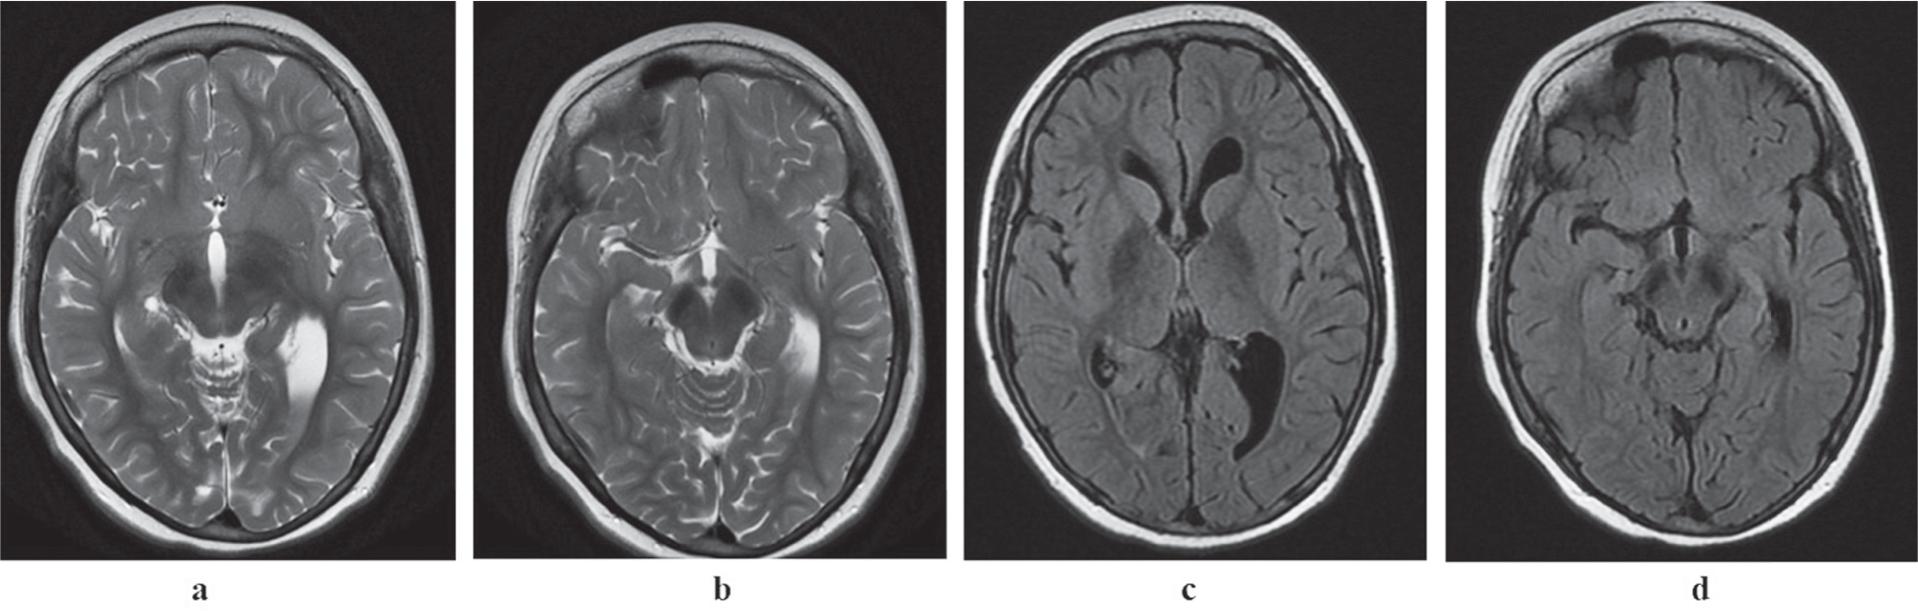

MRI scans at the age of eight years (Fig. 3) revealed iron deposits in the substantia nigra and globus pallidus. Neither abnormal myelination nor atrophy of the corpus callosum and the brainstem was identified.

Iron accumulation in the substantia nigra and globus pallidus in T2-weighted (a, b) and FLAIR (c, d) scans